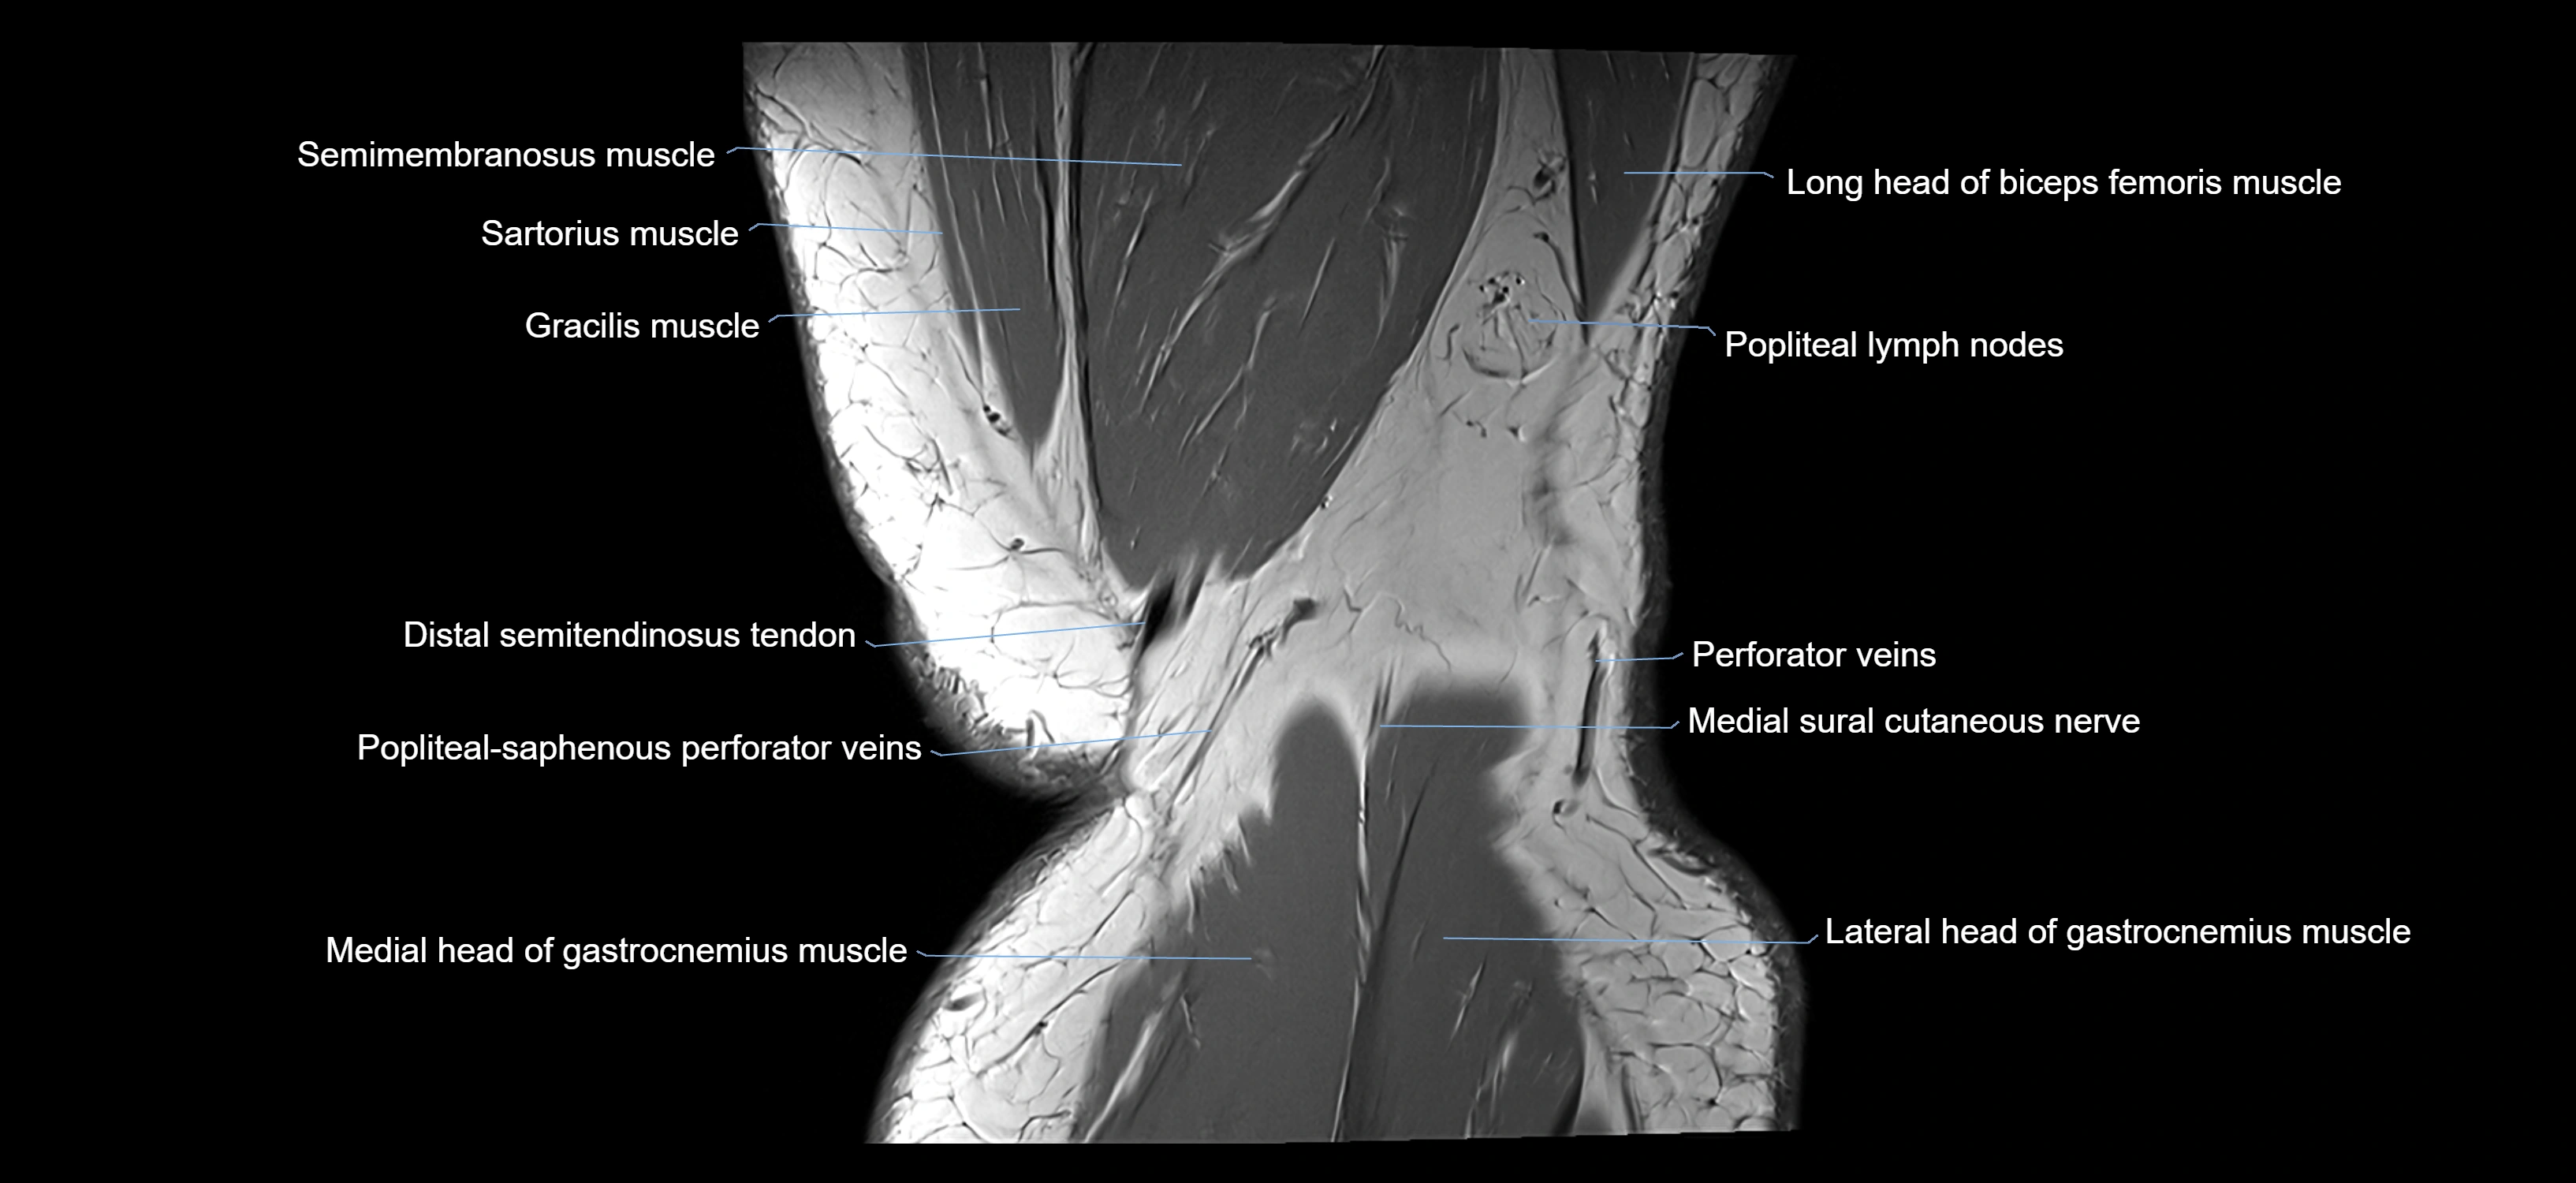

- Semimembranosus muscle

- Sartorius muscle

- Popliteal lymph nodes

- Popliteal–Saphenous perforating veins

- Medial head of gastrocnemius muscle

- Lateral head of gastrocnemius muscle

- Medial sural cutaneous nerve

- Biceps femoris muscle (Long head)